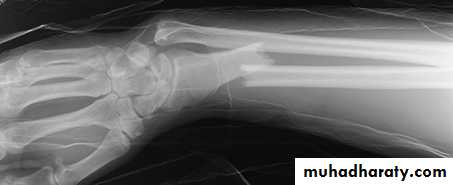

Galeazzi fracture dislocation of the radius

It is caused by fall on the hand , there is fracture in the lower third of the radius and dislocation of the inferior radio- ulnar joint .Clinically : it is much more common than monteggia , prominence and tenderness over the lower end of the ulna is an important point in examination .

Treatment : the most important point is to restore the length of the fractured radius , other wise the dislocation will not reduced .

In children close reduction is possible but if fail , then open reduction and fixation .

In adult , the treatment will be by open reduction and internal fixation .